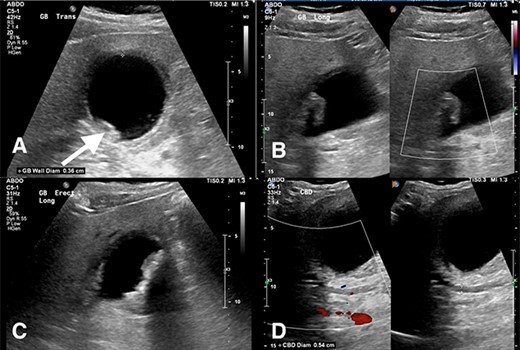

Abdominal ultrasound revealed a thickened gallbladder wall measuring 3.6 mm, mobile sludge, small amounts of pericholecystic fluid and a positive sonographic murphy’s sign (Fig. 1). As such, the diagnosis of acute cholecystitis was made, and the patient underwent a LC.

(A) Transverse view of the gallbladder showing a 3.6 mm wall diameter. Inferior arrow also shows small stones and sludge. (B) Longitudinal view of the gallbladder again showing mobile sludge. (C) Longitudinal view of the gallbladder showing a small amount of pericholecystic fluid. (D) Measurement of the CBD diameter at 5.4 mm (within normal limits).